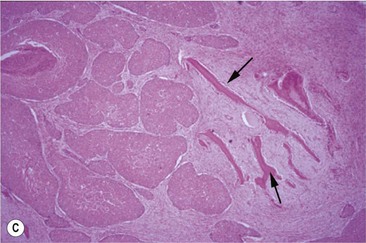

Oral SCC may involve the lips (Fig.11.13A), hard palate51 (Figs 11.13B,C), tongue51,52 (Figs 11.13D,E) or oral mucosa (Fig. 11.13F). It is also quite common for oral SCC to invade the nasal cavity and the paranasal sinuses (often to the point of gross distortion or obstruction to airflow).53 Some SCCs involve the base of the tongue (Fig. 11.13E) and pharynx (Fig. 11.13G) and can physically affect their function. Where the nasal cavity and paranasal sinuses are involved, there may be altered airflow (or even complete obstruction of the ipsilateral nostril). Horses with pharyngeal and lingual SCCs may present with dysphagia of progressive, insidious onset. In all cases, weight loss and poor general health are common.

Fig. 11.13 (A) A destructive carcinoma on the lip of a 23-year-old pony gelding. Note the extensive tissue destruction and the loss of the maxillary teeth. Treatment with intralesional cisplatin and topical 5-fluorouracil was not effective. (B) Facial distortion due to nasopalatine squamous cell carcinoma in a 12-year-old pony gelding. (C) A histologic section of the endonasal carcinoma shown in (B). Solid cords of squamous carcinoma are surrounded by fibrous stroma and trabeculae of non-neoplastic reactive bone (arrows). (D) Squamous cell carcinoma of the pharynx, which was identified some 3 months after a lesion had been detected in the hard palate. It is possible that this developed independently or that it was an extension of the earlier lesion. (E) Carcinoma of the free portion of the tongue. The local lymph node was enlarged (see J); slide courtesy of Dr R.R. Pascoe. (F) This highly destructive oral carcinoma developed in a 4-year-old Warmblood. It involved the maxillary bone and resulted in dental problems also.

(G) This horse was presented with weight loss and dysphagia. The highly destructive oral and invasive carcinoma was not visible endoscopically from the pharynx and was only seen with difficulty during an oral examination. (H) Photomicrograph of cords of solid squamous cell carcinoma with deep invasion of the tongue. (I) Metastasis of squamous cell carcinoma to regional lymph node showing cords of tumor cells (arrows) beneath cortical lymphoid tissue.

Pathology

Histologically, the tumor has distinctive characteristics with irregular cords of downward-invading neoplastic keratinocytes. (Figs 11.13H,I). A SCC characteristically has large amounts of non-neoplastic fibrous stroma in which inflammatory cells are plentiful. The abundant stroma results in a lesion that is characteristically tough or scirrhous when palpated or excised. The accumulation of variable amounts of keratin produces ‘keratin pearls’ in well differentiated tumors that can be used to define the likely malignancy of the lesion. Poorly differentiated carcinoma shows a more anaplastic cell structure, higher rates of division (high mitotic index), and much less keratin and, therefore, can closely resemble aggressive myxosarcoma. SCC is one of the better defined equine oral neoplasms.